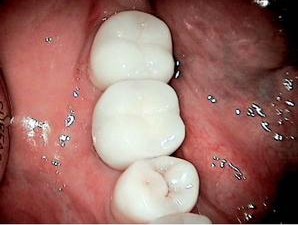

The implant offers an increase of $284 in gross production over the three-unit bridge, which is no big deal. However, you have provided a better and more permanent solution for your patient. Note that this example assumes that no extraction is needed, no site preservation is needed, there is good bone both vertically and horizontally, and adjacent teeth are not in need of restoration–essentially a perfect situation! This rarely presents itself in my practice. So, let’s consider a more realistic example, specifically the case that was presented pictorially in the last article. You may remember the “tired” molar that was failing with a fistula and hemisected roots. In that case, the patient would not entertain any removable solution, so I presented her with these fixed solutions for comparison:

Option 1: Traditional Three-Unit Bridge, $3,319 (including extraction at $121, two retainers at $1,000 each, pontic at $1,000, plus core build-up for distal retainer at $198). Option 2: Single Tooth Implant, $4,753 (including extraction at $121, site preservation $150, implant placement $1,822, abutment $462, crown $1,000; plus core build-up $198 and crown $1,000 to restore distal tooth).

Option 2 increases gross production by $1,434, or 43%! Now that is worth talking about! But perhaps more important is that you are offering your patient a better solution–one that is more permanent, offers better function, doesn’t result in bone loss over time, and won’t have to be replaced in five to ten years.